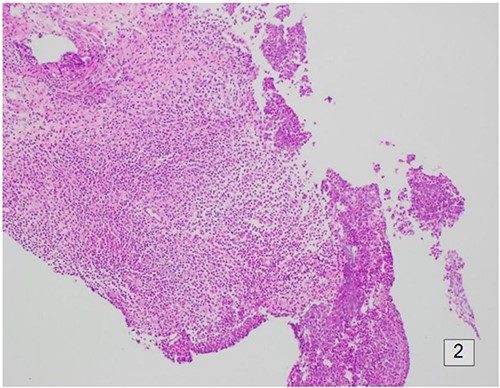

Following initial review, the patient was referred for a magnetic resonance image (MRI) which demonstrated an indeterminate retro-areolar lesion in the left breast (Fig. 2). A targeted ultrasound and core needle biopsy also showed active chronic periductal, interlobular and interstitial inflammation with focal duct ectasia consistent with Breast Imaging Reporting and Database System (BI-RADS) score of 2. Histological analysis showed predominant eosinophilic infiltrate (Fig. 3). There was no evidence of granulomatous inflammation or malignancy and staining for fungal elements and mycobacterium was also negative. A biopsy of the adjacent skin showed ongoing periductal and interstitial chronic inflammatory cell infiltrate with focal abscess formation (Fig. 4).

Histology of the surrounding breast tissue adjacent to the left retro-areolar complex.